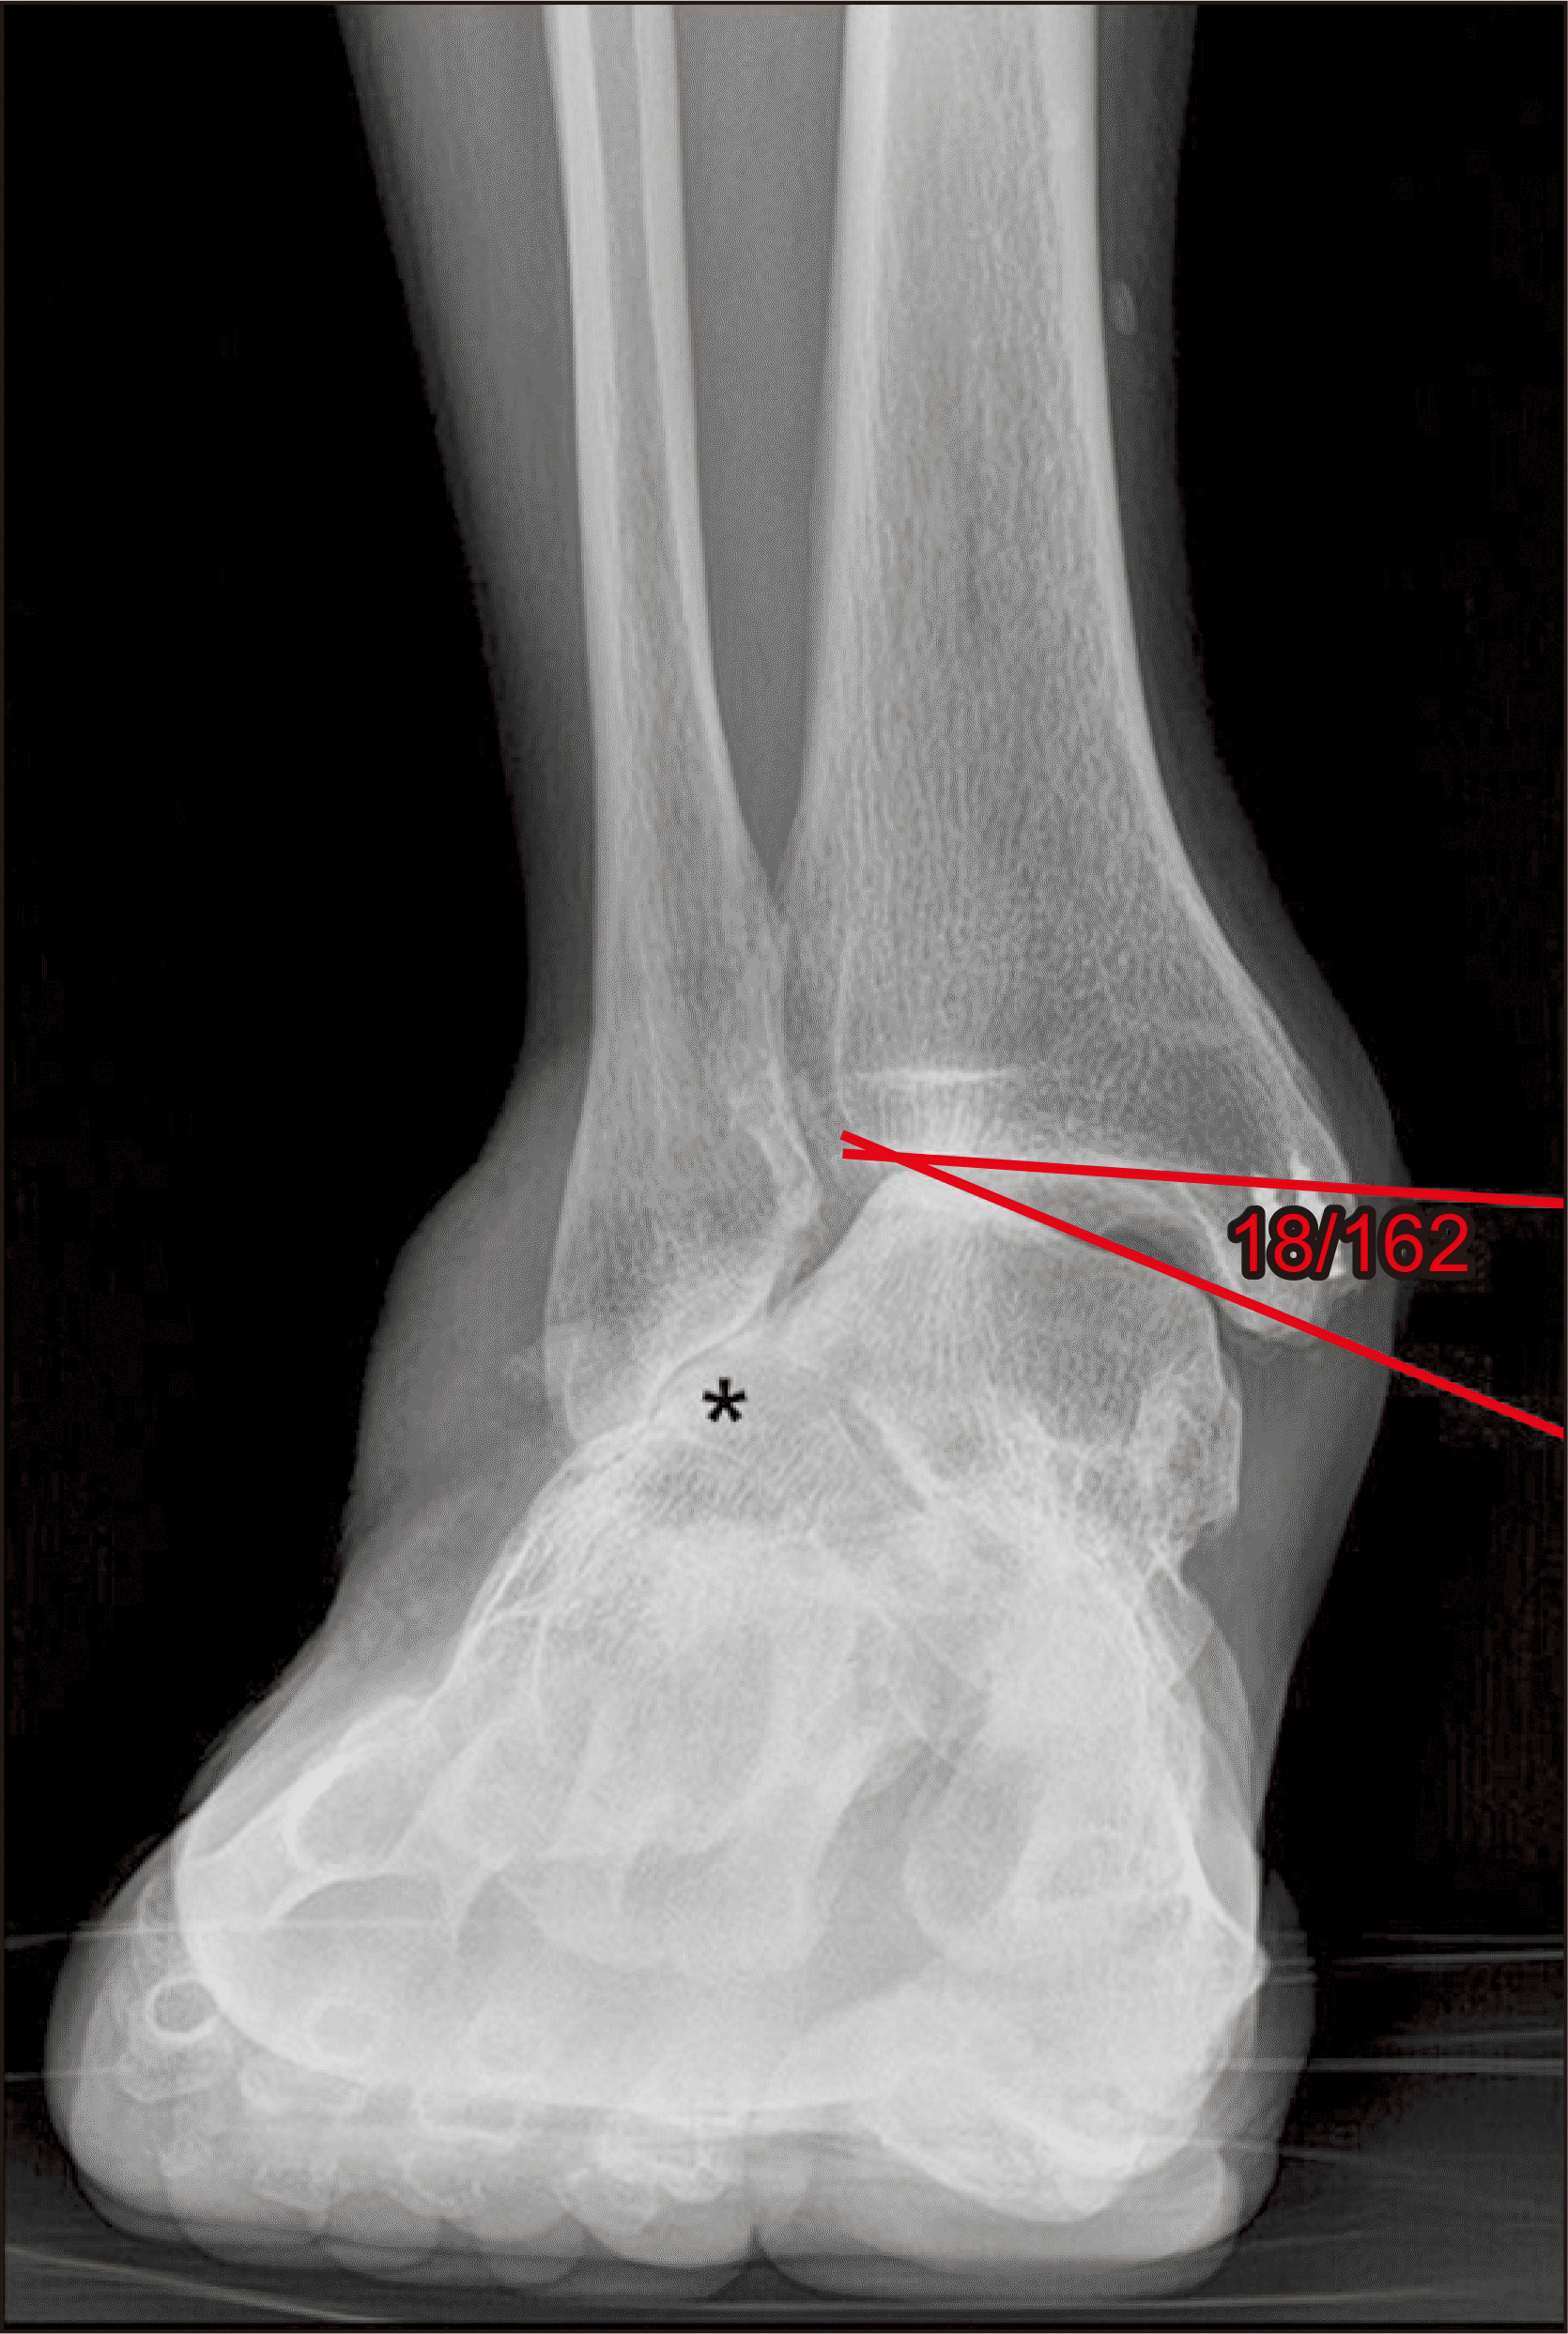

체중부하 방사선 촬영은 편평족의 진단에 있어 가장 표준이 되는 검사로, 체중부하 족부 전후면, 족부 측면, 족관절의 전후면 혹은 모티스 영상(mortise view) 및 후족부 정렬 촬영(hindfoot alignment view)8) 등이 진단을 위해 권고된다.9) 족부 전후면 사진에서는 전족부 혹은 중족부의 외전 정도를 평가할 수 있으며 거주상 관절 피복각(talonavicular coverage angle), 거주상 관절 이탈률(talonavicular uncoverage percent) 등 이를 반영하는 매우 다양한 지표를 측정할 수 있다(Fig. 1). 족부 측면 사진에서는 내측 세로궁의 소실 정도를 평가할 수 있는데, 흔히 쓰이는 지표로는 Meary angle이라 불리는 외측 거골-제 1중족골 각도를 측정할 수 있다(Fig. 2). 또한 족부의 내측주(medial column) 관절들의 족저부 벌어짐(plantar gapping) 정도를 확인하여 내측주 불안정성 정도를 평가할 수 있으며 족근동에서 거골과 종골의 직접적인 충돌 혹은 족근동 주변 골의 경화소견이나 낭종성 병변 등을 통해 족근동 충돌을 간접적으로 확인할 수 있다(Fig. 3). 족관절의 전후방 혹은 모티스 사진에서는 거골의 외반경사(valgus talar tilt)의 유무를 통해 족관절의 불안정성을 평가할 수 있으며 변형이 많이 진행한 경우 비골하 충돌 또한 확인할 수 있다(Fig. 4). 마지막으로, 후족부 정렬 촬영을 통해서는 후족부 외반 변형의 정도를 평가할 수 있는데, 주로 후족부 정렬각(hindfoot alignment angle) 혹은 후족부 모멘트암(hindfoot moment arm)을 측정한다(Fig. 5).10)

새로운 분류체계는 변형의 종류와 위치에 따라 A~E로 나누고, 각 변형의 유연성 유무에 따라 1기 유연성 변형과 2기 강직성 변형으로 분류하였다(Table 2).6) 이러한 변형은 진찰 소견과 체중부하 단순 방사선 촬영을 통해 평가하도록 하였고, 체중부하 전산화 단층촬영의 경우 아직 전세계적으로 사용되고 있지는 않기 때문에 판단기준에서 제외되었다. A형 변형은 후족부 외반 변형으로 후족부가 신체의 정중선으로부터 외측으로 전위된 변형을 뜻한다. 임상적으로 진찰 시 후족부 외반이 관찰되거나, 후족부 정렬 영상에서 후족부 정렬각 혹은 후족부 모멘트암의 증가 등으로 판단할 수 있다(Fig. 5). B형 변형은 전족부 혹은 중족부의 외전 변형으로 전족부나 중족부가 후족부를 기준으로 외측으로 전위된 변형이다. 체중부하 족부 전후면 사진상 거골두에 대한 주상골의 피복(coverage) 정도가 감소하고, 거주상 관절 피복각이 증가한다(Fig. 1). 또한 이 변형에 의해 족근동 충돌이 발생할 수 있으며, 족근동 주변의 압통 및 통증이 발생할 수 있다. 체중부하 족부 측면사진상 족근동에서 거골과 종골의 직접적인 충돌 소견이 보이거나, 족근동 주변의 거골과 종골의 골경화 혹은 골낭종 등을 통해 간접적으로 확인할 수 있다(Fig. 3). C형 변형은 전족부의 내반 변형 혹은 내측주 불안정성으로 임상적으로 후족부를 중립 위치에 고정한 뒤 관찰하였을 때 전족부가 내반을 보이는 변형이다(Fig. 8). 일부에서는 이를 회외 변형으로 불러야 한다는 의견도 있으나 현재 혼용해서 쓰이고 있다.11,20) 내측주 불안정성은 체중부하 족부 측면사진상 거주상 관절, 주상설상 관절(naviculocuneiform joint) 및 족근중족 관절(tarsometatarsal joint)이 배측 불안정증을 보이는 것으로, 영상검사상 족저부 벌어짐 유무 등을 통해 내측주 불안정성의 유무 및 위치를 확인할 수 있다(Fig. 3). D형 변형은 거근관절의 탈구 혹은 아탈구 변형으로 거골이 종골을 기준으로 내회전, 족저굴곡되면서 종골은 거골을 기준으로 외회전, 외반, 외측 전위가 발생하면서 거골하 관절의 아탈구가 발생하고, 심한 경우 비골하 충돌을 일으키게 된다(Fig. 4). E형 변형은 발목관절의 외반 변형이 발생한 경우이며, 족관절의 전후방 혹은 모티스 사진에서 거골의 외반경사로 확인할 수 있다(Fig. 4). 이 분류의 적용은 한 환자에 대해 A 부터 E까지의 변형 유무를 확인하고, 각각의 변형이 유연성 변형인지, 강직성 변형인지에 따라 1기와 2기를 나누는 방식으로 적용한다.

Figure 4

Weight bearing ankle anteroposterior radiograph showing valgus talar tilt and subfibular impingement (*).